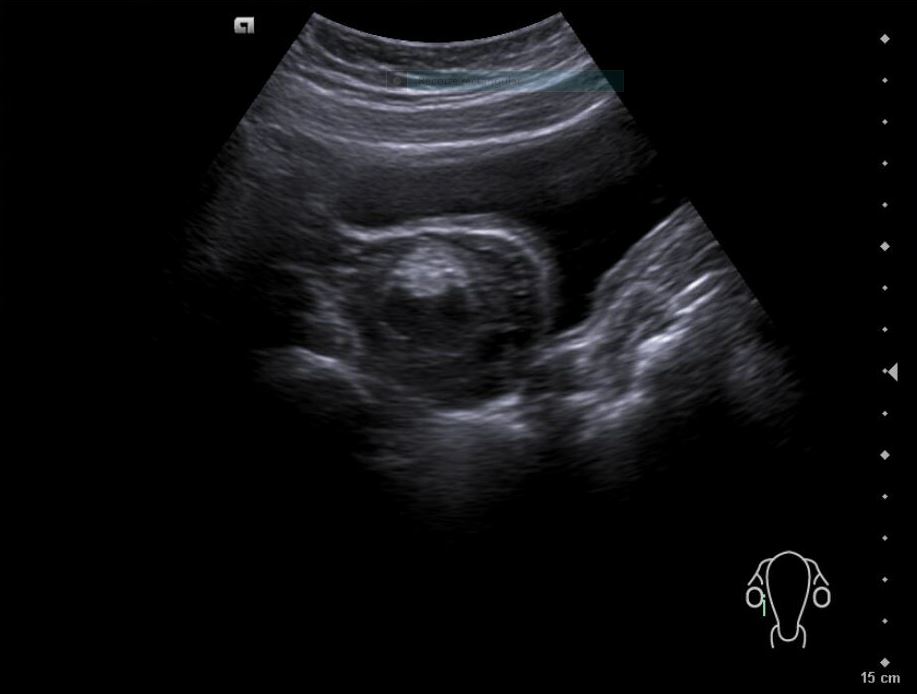

• Revisión ginecológica incidental muestra una imagen heterogénea en anexos: masa de aspecto solidoquístico en ovario derecho (43 × 33 mm), con zona hiperecoica y posible componente quístico. Se plantea teratoma como primera hipótesis diagnóstica.

La paciente es valorada en consulta presencial de ginecología. Ecografía vaginal confirma:

• Formación sólidoquística en anexo derecho de 43 × 33 mm con signos sugestivos de teratoma.

• Lesión quística densa adyacente de 6 mm (endometriosis o componente adicional del teratoma).